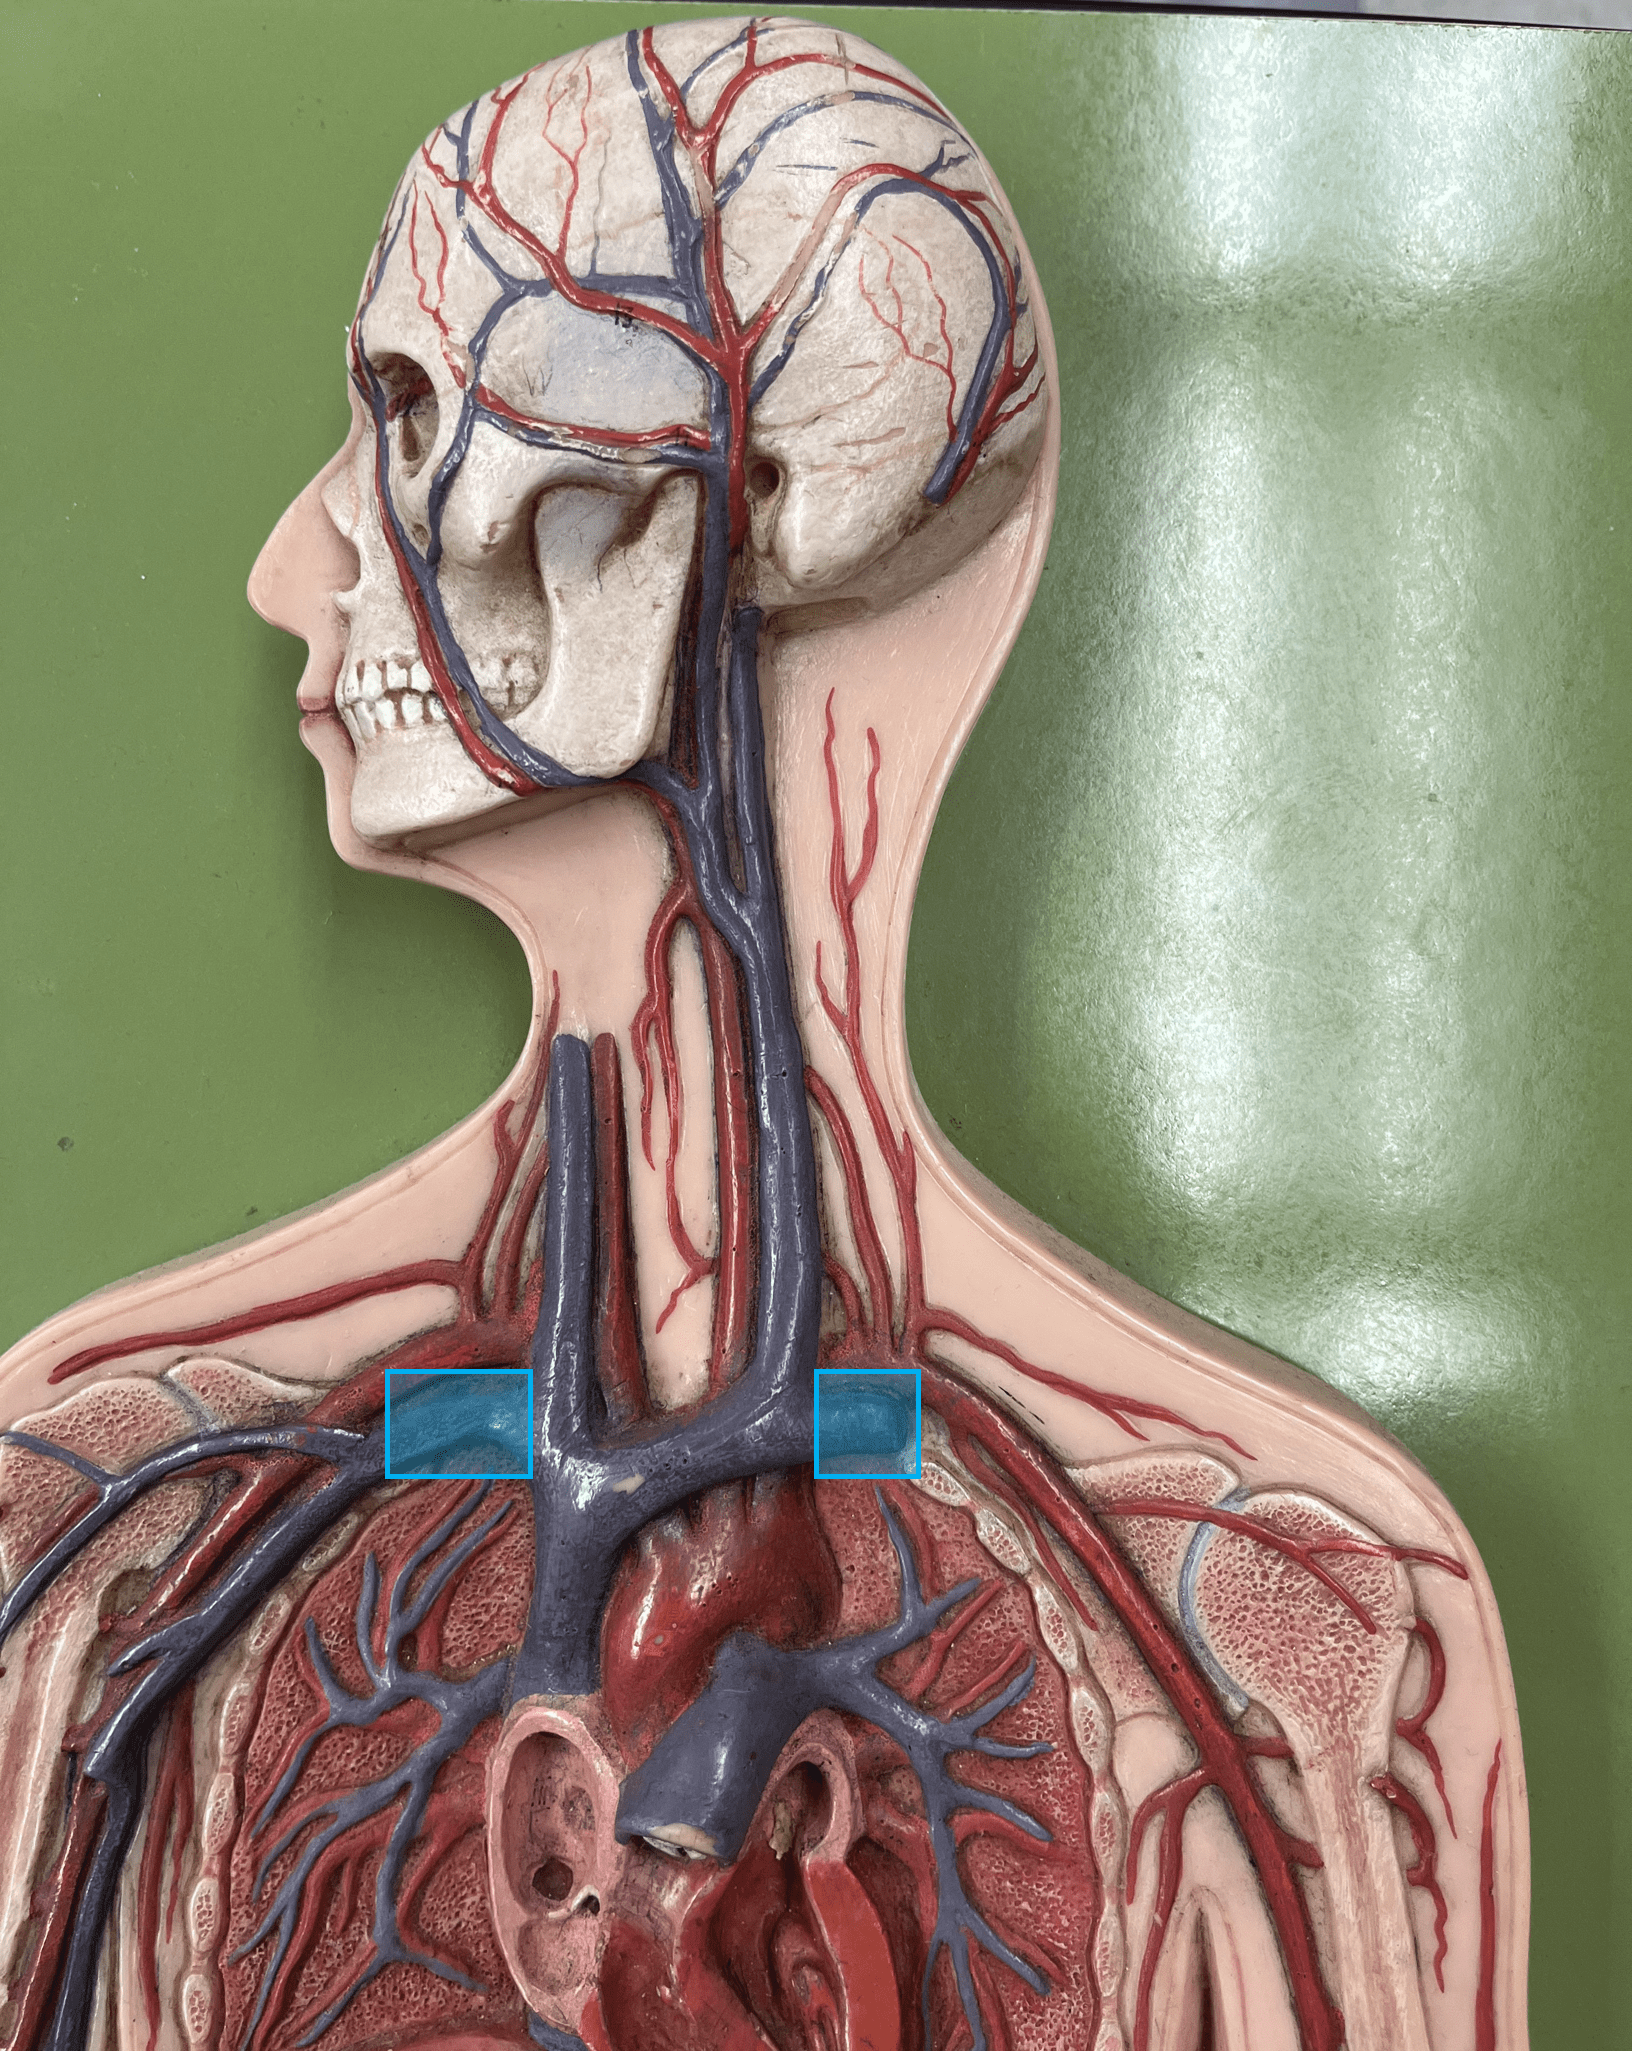

brachiocephalic vein

• A vein of the thorax.

• Drains the subclavian, external jugular, vertebral, internal jugular, and left intercostal (1-3) veins.

• Empties into the superior vena cava.

• Drains the subclavian, external jugular, vertebral, internal jugular, and left intercostal (1-3) veins.

• Empties into the superior vena cava.

subclavian vein

• A vein of the thorax.

• Drains the axillary vein.

• Empties into the brachiocephalic vein.

• Drains the axillary vein.

• Empties into the brachiocephalic vein.

superior vena cava

• A vein of the thorax.

• Drains the azygos and brachiocephalic veins.

• Empties into the right atrium.

• Drains the azygos and brachiocephalic veins.

• Empties into the right atrium.